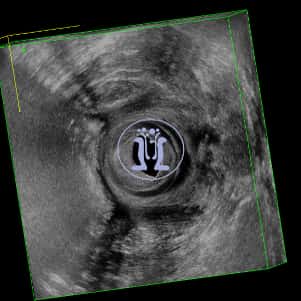

Ενα συριγγιο πρωκτού σε 45 χρονών ασθενή με πολλαπλά δερματικά στόμια δεξιά και αριστερά. Το πρωκτικό στόμιο είναι στην 6η ώρα σε εν τω βαθει επίπεδο, σε απόσταση 21 mm από την είσοδο του δακτυλίου.

Τα στόμια επικοινωνούν μεταξύ των και παρουσιάζουν εκροή υγρού. Η όλη κατάσταση εμφανίσθηκε μετά από παροχέτευση εκτεταμένου περιεδρικού αποστήματος που έδωσε την εντύπωση γάγγραινας Fournier. Η κλινική και υπερηχοτομογραφικη εικόνα ειναι χαρακτηριστική πεταλοειδούς συριγγίου.